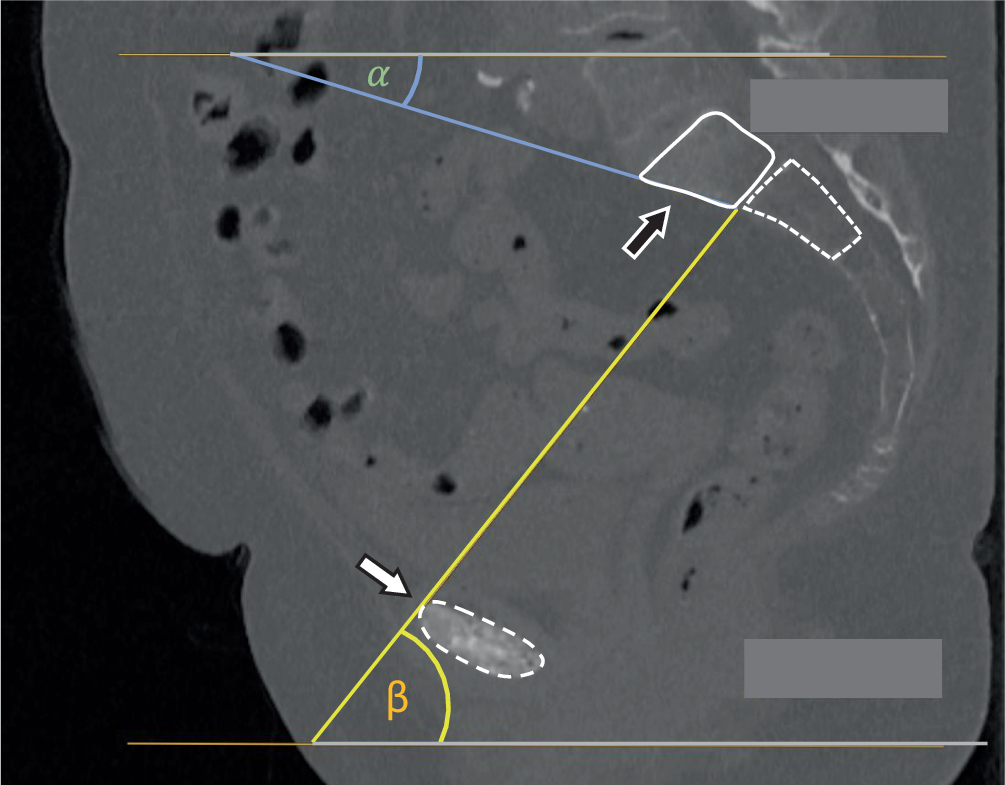

• Employ the diagnostic CT to measure the angles for the personalized inlet and outlet view, which are critical aspects of the presented method (Fig. 1). A comprehensive explanation of the personalized inlet and outlet angles is illustrated in appendix 2

Fig. 1

Determination of the personalized inlet angle (α) and personalized outlet angle (β) in the sagittal view. The dashed line encircles the bony part of the symphysis, the solid line encircles the sacral vertebral bodies, the black arrow points to the S1 body